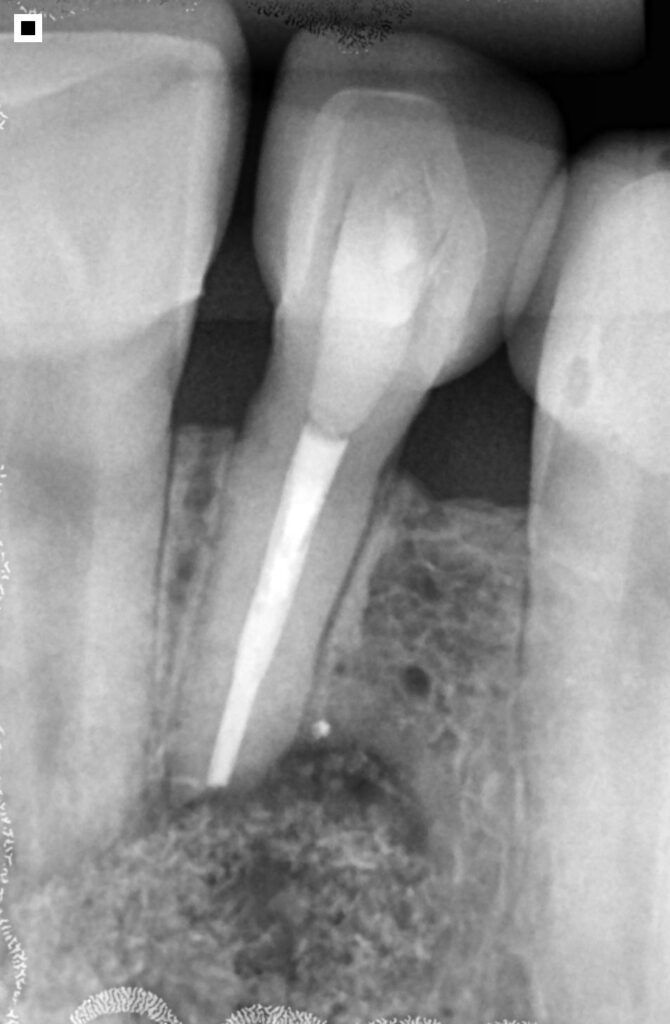

O diagnóstico da necessidade de uma apicectomia se baseia na avaliação clínica e nos exames de imagem. A radiografia e a tomografia computadorizada visualizam com precisão a extensão da lesão.

No caso citado, os exames mostraram claramente a presença de uma lesão no ápice do dente, tanto na região lateral quanto central da raiz, confirmando a necessidade de intervenção cirúrgica.

Uma incisão na gengiva com bisturi, permitindo acesso à região óssea. A exposição da área infectada muitas vezes já revela a gravidade da lesão, seguida da drenagem do conteúdo infeccioso, quando presente.

Depois, é feita uma curetagem cuidadosa, removendo todo o tecido inflamado ou contaminado ao redor da raiz e o corte da ponta do ápice radicular, eliminando a porção comprometida. Com a área limpa, pode-se aplicar o enxerto ósseo, geralmente com biomaterial associado a técnicas modernas de regeneração.